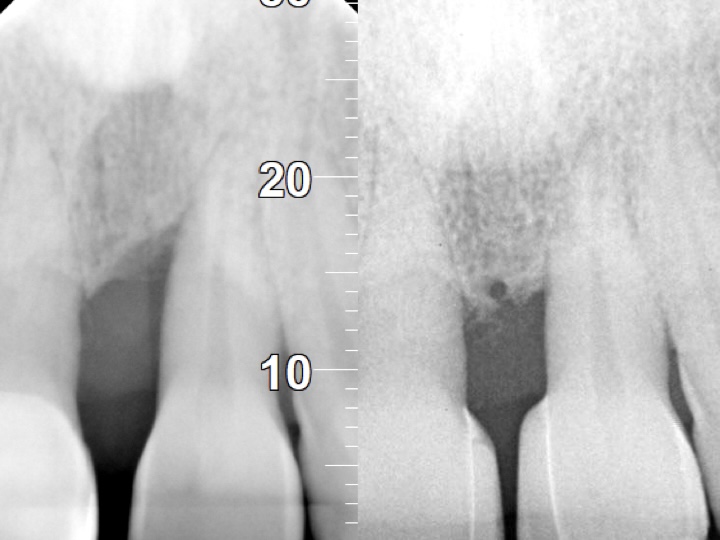

- Radiographic Bone Levels: X-rays assess supporting bone structure.

- Periodontitis: Plaque hardens into tartar, gum tissue recedes, pockets deepen, and mild to moderate bone loss may occur.

- Advanced Periodontitis: Progressive deterioration of gum, bone, and periodontal ligament; teeth may feel loose, with moderate to severe bone loss.